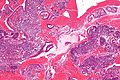

Secretory phase endometrium

Secretory phase. H&E stain. | |

Secretory phase endometrium, abbreviated SPE, is a common diagnosis in endometrial specimens.

Microscopic

Mid secretory phase

Features - post-ovulatory day 6-8:[1]

- Glands: Mucus in glands.

- Stroma: Edema (empty space around the glands).

The sections show endometrium with a normal gland-to-stroma ratio. The glands are mildly dilated, tortuous and have mucus within them. The glandular epithelium is simple and non-pseudostratified. The stroma is edematous and has a decidual reaction. No mitotic activity is apparent.